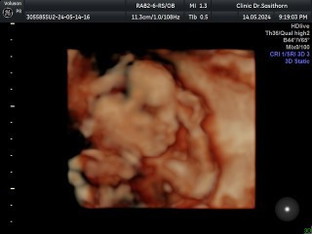

แม่ดูปฎิทินจีนมาตรงเด๊ะเลยค่ะ 5555 ไปหาคุณหมอมาแล้วบอกน้องเป็นผู้หญิง ในใจแม่อยากได้ผู้ชายแต่ไม่เป็นไรค่ะได้ลูกสาวก็ดี ❤😁 20 w 💕